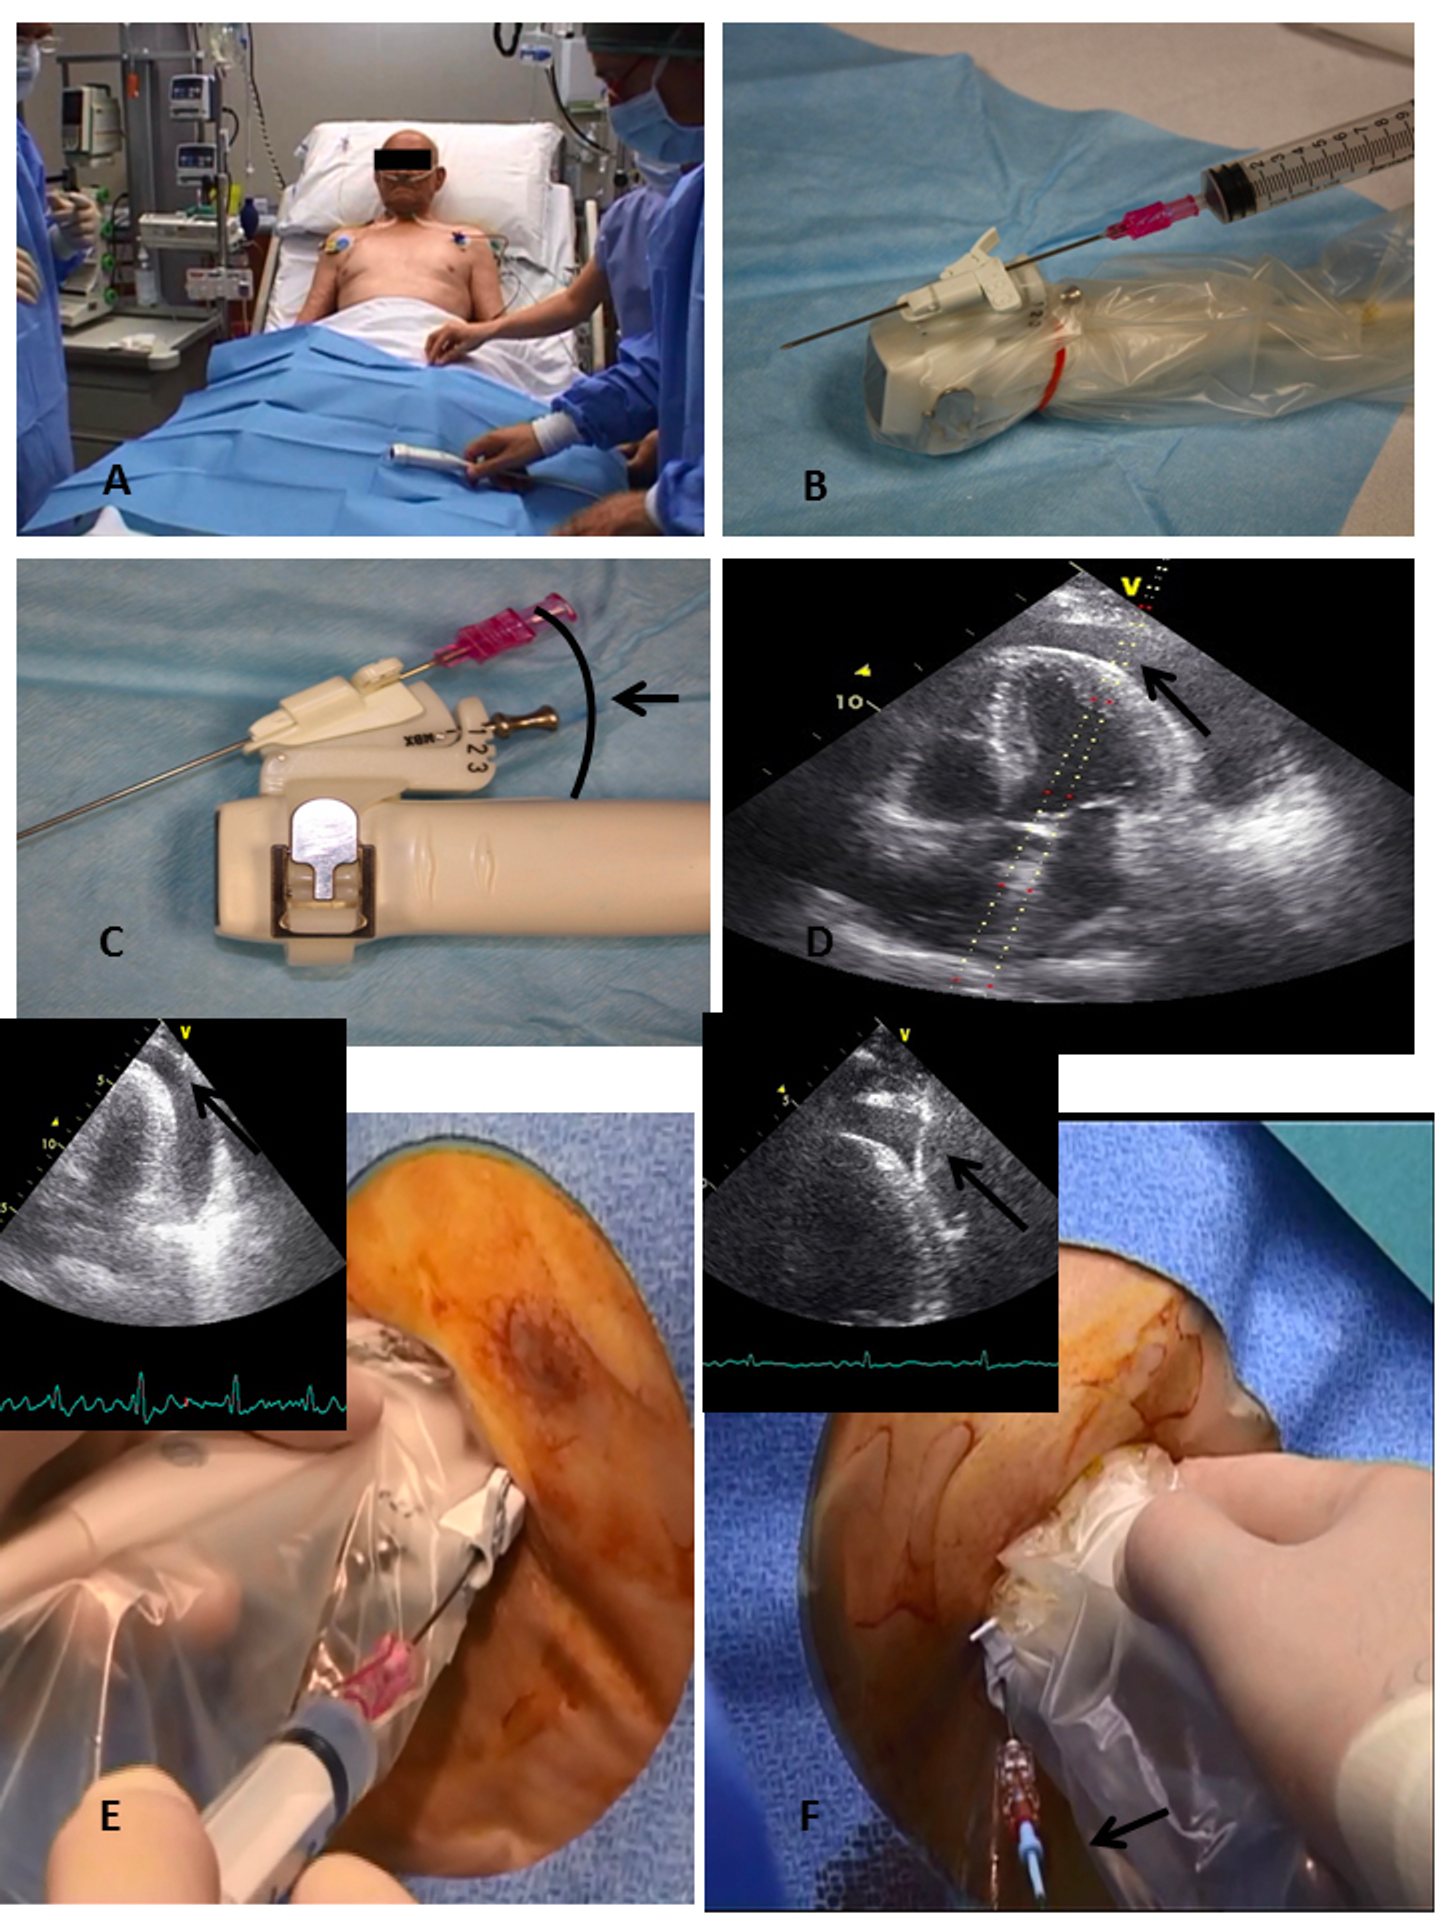

図2. Place the patient in a semi-reclining position (Panel A), use a probe-mounted needle covered with a sterile sheath (Panel B), choose the proper angle for the needle (Panels C and D), advance the needle slowly in aspiration through the tissue until there is a continuous visualisation of the tip (black arrow) (Panel E), introduce a J-tipped wire into the needle under continuous visualisation (black arrow) (Panel F).